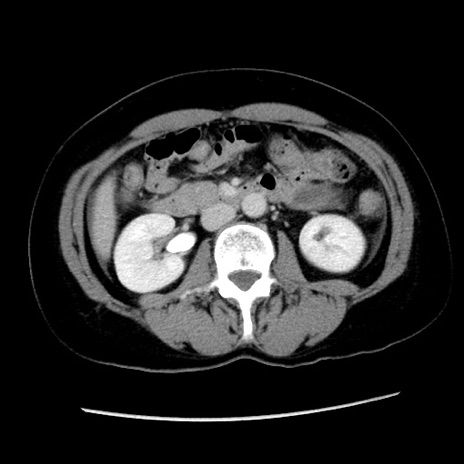

冠状断像

【症例】 50歳代女性

【主訴】 腹痛

【現病歴】前日生レバーを食べた。今朝に排便あり。 昼前に突然発症の腹痛を生じ、当院救急外来を受診した。

【既往歴】 子宮筋腫にてで子宮全摘後

【身体所見】 意識清明、腹部:平坦、軟、下腹部やや左を中心に圧痛・反跳痛あり、筋性防御あり

【データ】WBC 7800、CRP 0.07